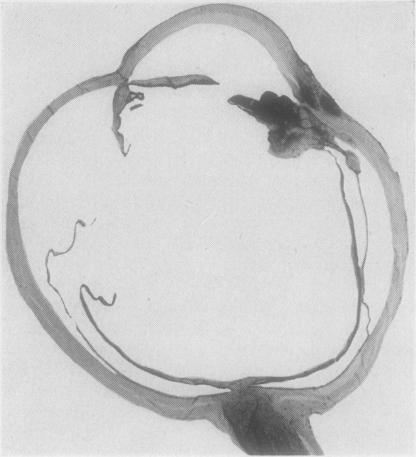

Ophthalmia nodosa due to caterpillar hairs.

Br J Ophthalmol. 1955 May;39(5):301-6. doi: 10.1136/bjo.39.5.301.